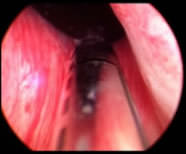

Es importante rotar la fibra siempre sobre el área a tratar y no “enterrarla” dentro del tejido (Fig. 3). El enterrar la fibra en el tejido implica, en primer lugar, que la ablación no tenga tanto efecto, debido a que las burbujas de vapor de agua rebotan, y en segundo lugar, se incrementaría la degradación de la propia fibra, ya que no habría fluido suficiente para su correcta refrigeración.

| Aproximación del extremo de la fibra al tejido prostático | |

![]() |

| Fig.3 | |

| Posicionamiento de la fibra | |

| * Cerca pero no en contacto con el tejido | |

| * Maximiza el efecto ablativo de la fibra | |

| * Prolonga potencialmente la vida de la fibra | |

| Rotación de la fibra | |

| * Ha de hacerse despacio. La tendencia es la de rotar la fibra demasiado rápido | |

| * Crítico a la hora de conseguir la máxima ablación | |

| * Permite suavizar el efecto en tejido (menos » tiras o pelusas» de adenoma) | |

| * Disminuye potencialmente el sangrado | |